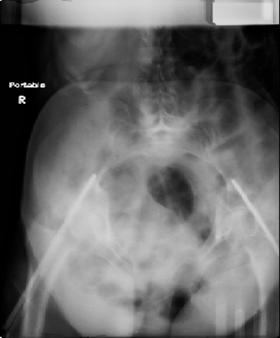

attached are images of a 70 year old female after peds versus car. her own car ran her over.

injuries are limited to the pelvis. left rami open and visible in a 10cm vertical laceration just lateral to left labia majora. wound is grossly clean. no vaginal and no urinary issues. CT scan shows widening of both SI joints anteriorly but I think this is vertically stable pattern.

pt treated that night with I/D and supra-acetabular frame to close the ring. consideration was given for SI screws bilateraly, but given time of night and other factors decision made not to proceed.

so the question is what next operatively if anything? concerns are infection, nonunion anteriorly and possible incompetence of the pelvic floor which may lead to prolapse issues. right rami are comminuted and plating may entail ilioinguinal approach to extend plate laterally to right iliac wing. retrograde screw up right rami is an option but I am not convinced it will add much. adding SI screws very doable, but major concern is restoring anterior ring. so far wound is clean and closed over a drain, and I have no plans to open it back up and wash again.

maintaining pelvic alignment in ex-fix in 70 yo female for any length of time may be challenging.

any thoughts? would anyone plate the pubic symphysis to close the gap and leave the more lateral rami fractures alone? the most recent pelvic case on this website involved pts with suprapubic catheters and antibiotic options including resorbable beads. I wonder how many people would plate and place antibiotic beads. thanks.